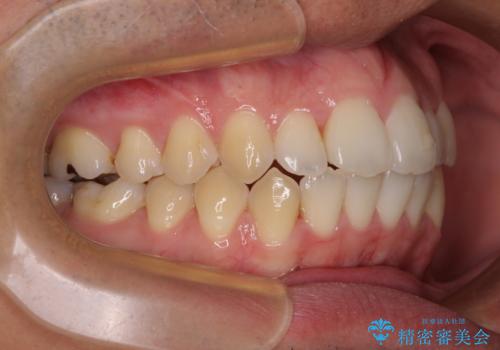

開咬とデコボコを整える インビザライン矯正治療

- 前歯の開咬と叢生を気にして来院された患者様です。

開咬の治療は、前歯を閉じるように動かすとともに、上下臼歯を圧下(骨内にめり込ませる)させることで進めて行きます。

インビザラインは臼歯の圧下を効果的に行えるため、インビザラインを用いて矯正治療を行うこととしました。また、アンカースクリューを用いて、口元の突出感の改善を図りました。